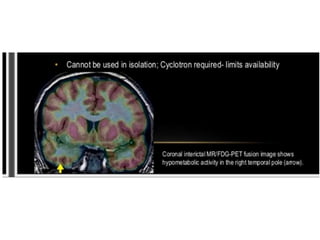

Temporal lobe epilepsy is characterized by seizures originating in the temporal lobe. It is the most common localization-related epilepsy, accounting for around 60% of such cases. Mesial temporal lobe epilepsy is the most frequent form, often caused by hippocampal sclerosis. Auras are common and can include epigastric sensations, cephalic sensations, anxiety, hallucinations and more. Automatisms like lip smacking or gesturing often occur during seizures. Around 60% of temporal lobe epilepsy patients respond well to antiepileptic drug treatment, while the remaining 40% have drug-resistant epilepsy and may require surgery.